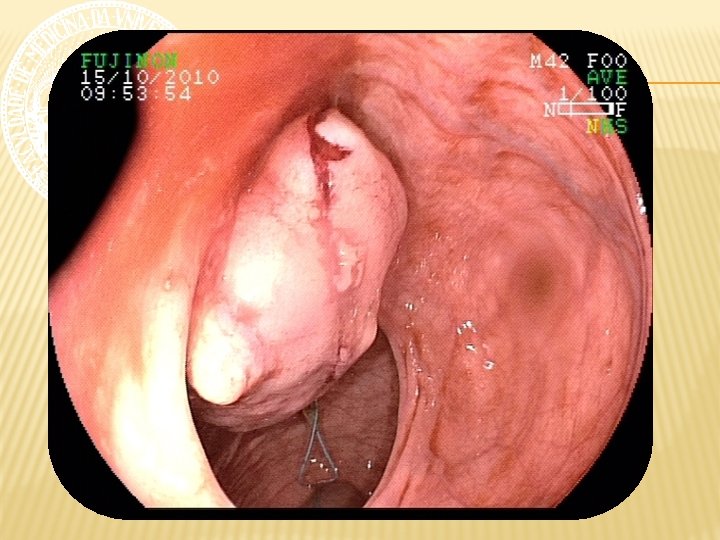

ENTEROSCOPIA RETRÓGRADA Nota-se em reto médio, a 15 cm da borda anal, LESÃO ELEVADA, pediculada, com superfície ulcerada, recoberta por fibrina e hematina, de aspecto subepitelial, medindo cerca de 4 cm de diâmetro. A 20 cm da borda anal, presença de ANASTOMOSE ileorretal, com algumas pequenas ulcerações, recobertas por delgada camada de fibrina, com fios de sutura, sem sinais de sangramento ativo e/ou recente. Íleo percorrido por cerca de 40 cm, não se observando alterações da mucosa. Realizada aplicação de endoloop, seguida de POLIPECTOMIA, sem intercorrências.

ENTEROSCOPIA RETRÓGRADA CONCLUSÃO 1. Colectomia total com ileorretoanastomose. 2. Ulcerações rasas em anastomose sem sinais de sangramento. 3. Lesão pediculada ulcerada em reto médio com sinais de sangramento recente. Polipectomia. 4. Íleo distal sem lesões.